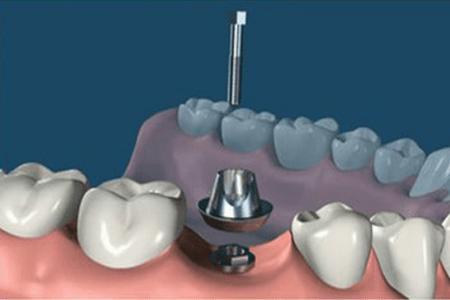

step2.

正式开始种植牙手术。在牙槽骨上制备一个孔,植入人工种植体。将牙骨床内严密缝合,大约一个星期后可以拆线。这次大概2个半月--3个月)

step4.

安装愈合基台,使种植体穿出牙龈,等待软组织成形。

step5.

在差不多2--3周后,软组织成形后。种植牙医生会用永久基台换下愈合基台。